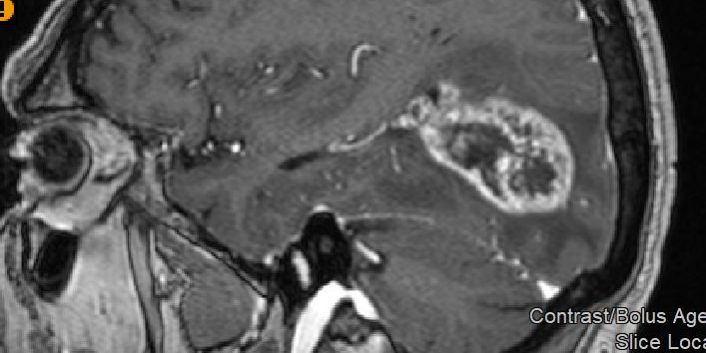

Ασθενής άνδρας, 65 ετών ο οποίος παρουσίασε αρχικά αίσθημα κόπωσης και διαλείπουσες κεφαλαλγίες. Ο νευροαπεικονιστικός έλεγχος με μαγνητική τομογραφία με σκιαγραφικό ανέδειξε χωροκατακτητική εξεργασία στην περιοχή του αριστερού σφηνοειδούς λοβίου με επέκταση και υποεπενδυματική διήθηση του ινιακού κέρατος.

Η μετεγχειρητική μαγνητική τομογραφία εγκεφάλου )βλ. εικόνα) εντός 48ωρου επιβεβαιώνει την ολική εξαίρεση του όγκου.